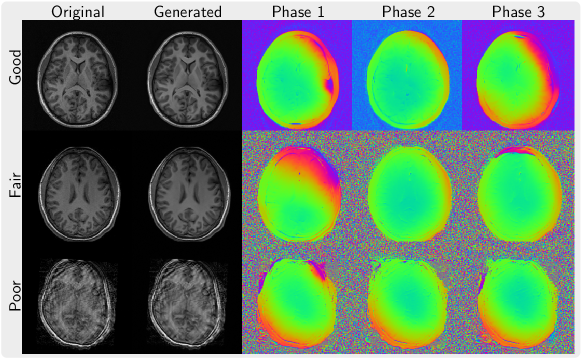

Figure 2(a) shows three magnitude images of different quality from the ABIDE dataset and the corresponding magnitude and phase maps of complex-valued images generated by phase augmentation. The magnitude part of the generated images stays very close to the original image but exhibits a bit less noise. The phase of the generated images maps is smooth and looks realistic with some random variations as expected.

In Figure 2(b), we present the magnitude and phase from images reconstructed using PICS with ESPIRiT sensitivities and NLINV using the same PSC prior for 8.2-times undersampled Poisson-disc k-space data in comparison to a zero-filled image and fully-sampled reference. For both methods, similar reconstructions with excellent quality can be obtained for this prior for linear and non-linear reconstruction. This prior trained from a small dataset of complex-valued images will serve as a baseline for the other learned priors.